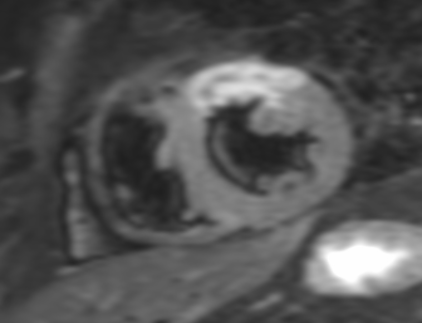

Darstellung des Herzmuskelgewebes

Angeborene Erkrankung der rechten Kammer

Angeborene Herzmuskelverdickung